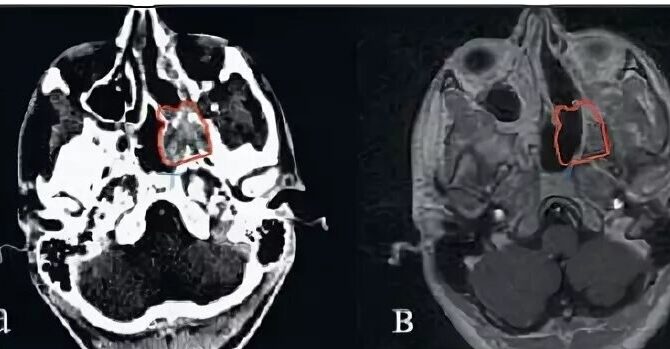

Ребенок поступил во владимирскую ОДКБ с жалобами на затрудненное дыхание через нос и обильное носовое кровотечение. Врачи поставили жутковатый диагноз – юношеская ангиофиброма основания черепа. Об этом сообщили в сообществе больницы во «ВКонтакте».

Юношеская ангиофиброма основания черепа – это доброкачественная опухоль, которая чаще всего встречается у мальчиков-подростков 9-19 лет. Опухоль опасная, агрессивно растущая. Основные симптомы: затруднение носового дыхания, кровотечения из носа, нарушения слуха, деформация лицевого скелета, зрительные и глазодвигательные нарушения. Ангиофиброма может привести к смерти.

Фото: ОДКБ